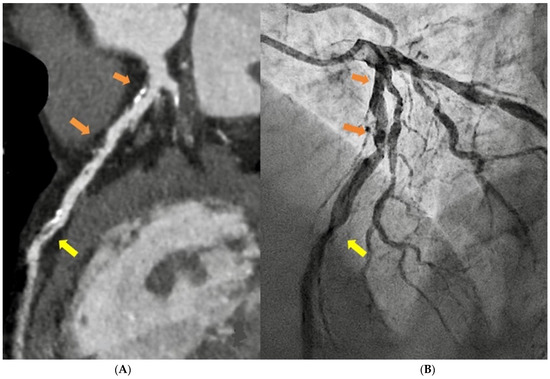

1.1. Computed Tomography

- Cademartiri, F.; Casolo, G.; Clemente, A.; Seitun, S.; Mantini, C.; Bossone, E.; Saba, L.; Sverzellati, N.; Nistri, S.; Punzo, B.; et al. Coronary CT angiography: A guide to examination, interpretation, and clinical indications. Expert Rev. Cardiovasc. Ther. 2021, 19, 413–425. [Google Scholar] [CrossRef]

- Cury, R.C.; Leipsic, J.; Abbara, S.; Achenbach, S.; Berman, D.; Bittencourt, M.; Budoff, M.; Chinnaiyan, K.; Choi, A.D.; Ghoshhajra, B.; et al. CAD-RADSTM 2.0—2022 Coronary Artery Disease-Reporting and Data System. J. Cardiovasc. Comput. Tomogr. 2022, 16, 536–557. [Google Scholar] [CrossRef]

- Ferencik, M.; Mayrhofer, T.; Bittner, D.O.; Emami, H.; Puchner, S.B.; Lu, M.T.; Meyersohn, N.M.; Ivanov, A.V.; Adami, E.C.; Patel, M.R.; et al. Use of High-Risk Coronary Atherosclerotic Plaque Detection for Risk Stratification of Patients With Stable Chest Pain. JAMA Cardiol. 2018, 3, 144. [Google Scholar] [CrossRef]